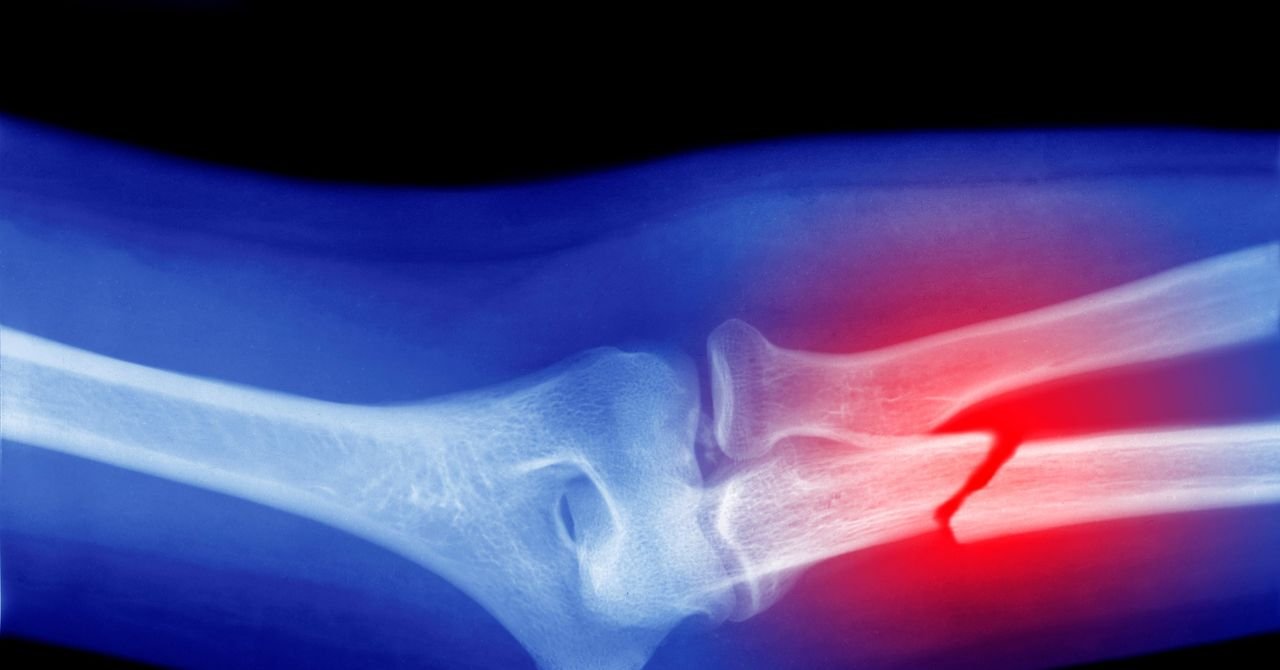

Your bones are re -filled throughout your life. Osteoporosis is a condition where this process goes wrong, it exceeds the rate that is replaced with bone breakdown. It weakens the bone over time and the fracture is more likely. Condition There are many risk reasons– Age, gender, ations, diet, smoking and alcohol and genetics are all known to influence it – over time it develops slowly. Often people do not understand that they have a condition until they break the bones.

This new analysis, published in the Osteoporosis International Journal, has added exposure to a potential new risk of microplastics. The study reviewed 62 scientific articles that tested various laboratories and animals on the bone micro- and nanoplastic potential effects. Lab test analysis has shown that microplastics stimulate the formation of osteoclasts, cells made by bone marrow stem cells that reduce the promotion of bone tissues to restore the restoration, the process that breaks the body and removes the old or damaged bone.

The survey also found that the bone related to the bone, plastic particles can reduce the functioning of the cells, premature cellular can induce aging, change the expression of genes and trigger inflammatory reactions. The combination of these effects produces an imbalance where the osteolasts destroy bone tissues more more than the resurrection, thereby weakening the bone structure severe.

When the animal looks at the study, the researchers found that the body reduces the calculation of the white blood cells in the body – which suggests the change in the bone marrow activity. Furthermore, this animal survey was suggested that the microplastic effect on the osteolasts could be associated with the degradation of bone microstructure and the formation of the irregular structure of the cell, increasing the risk of bone fragility, deformation and breakdown.